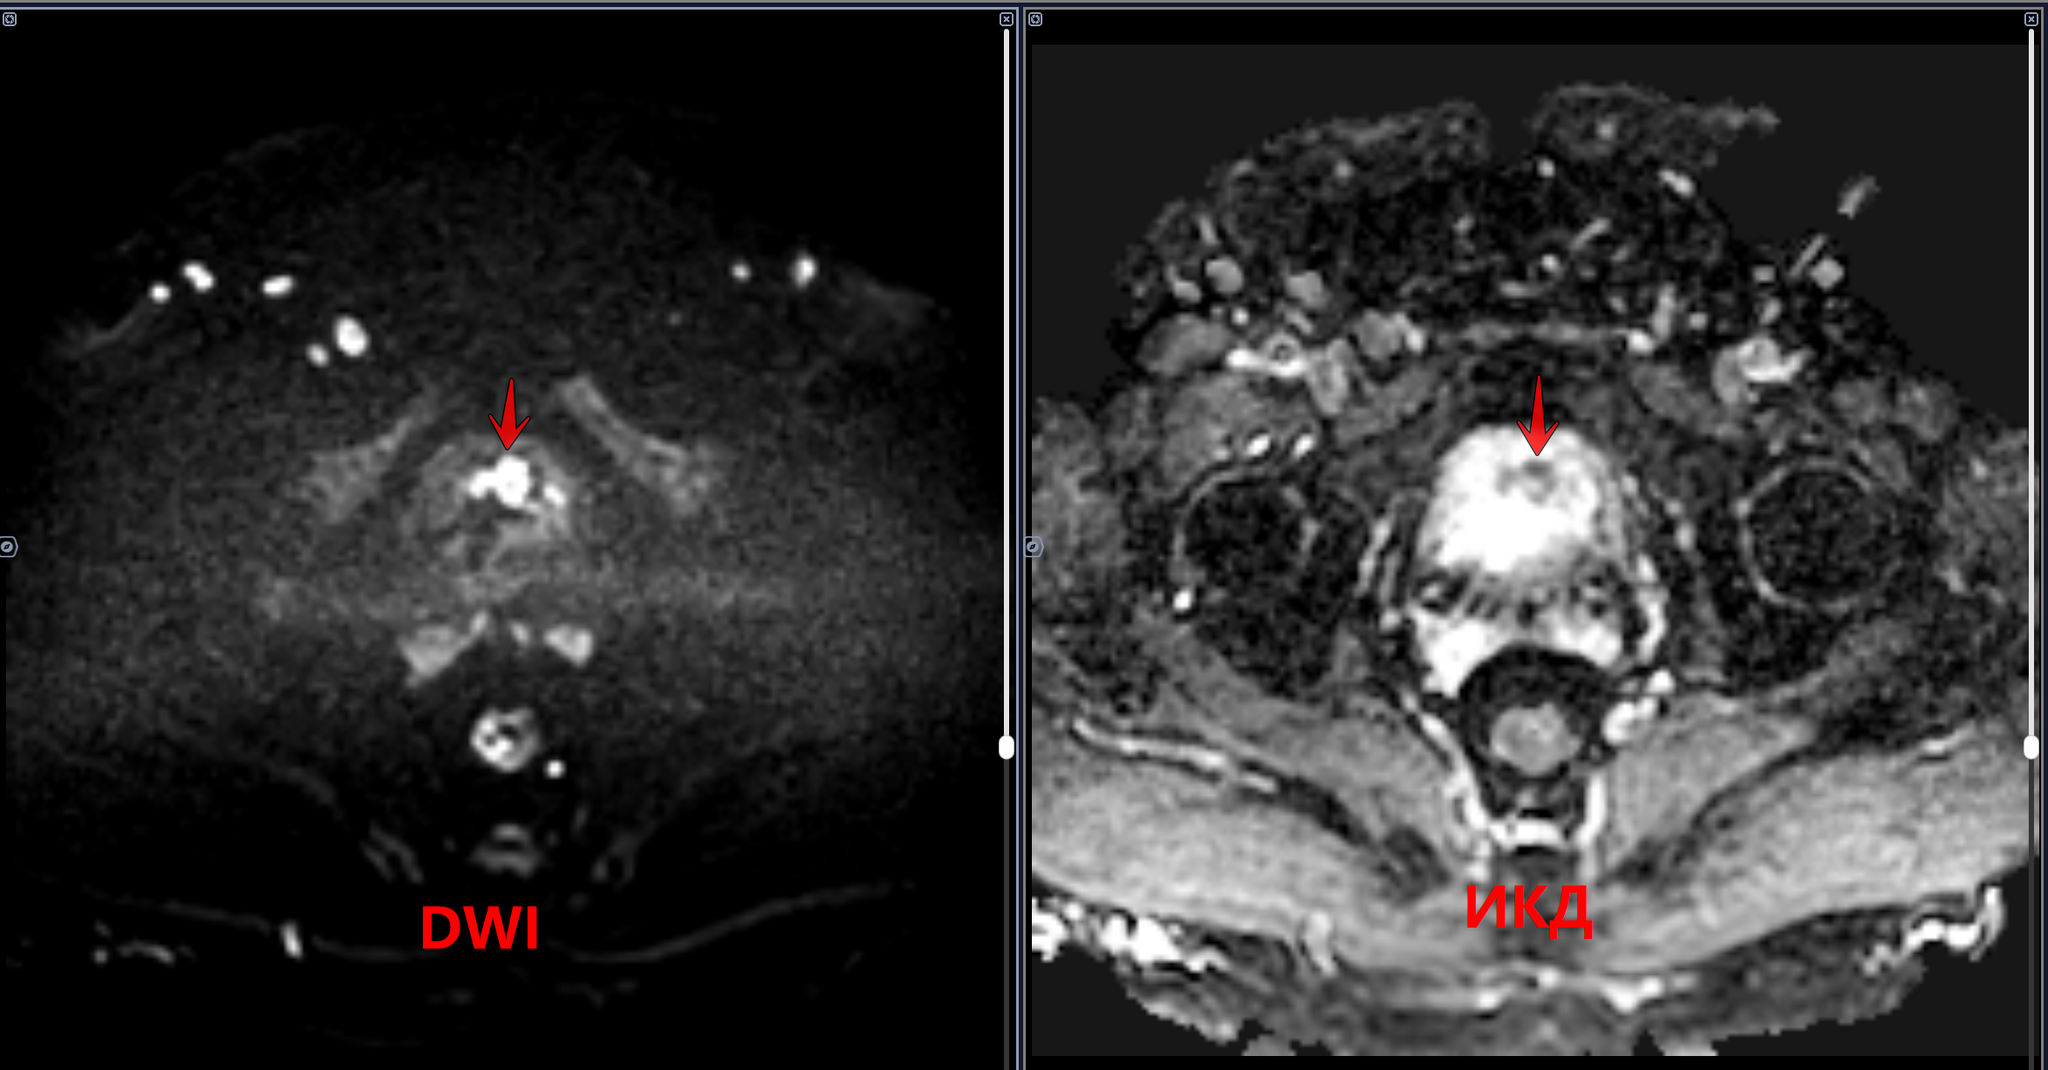

Мочевой пузырь заполнен умеренно, стенки его неравномерно утолщены, в полости визуализируется объемное солидное образования, с четкими, бугристыми контурами, исходящие: из левой боковой и частично задней стенок на 12-18 часах условного циферблата в аксиально проекции, прорастающее все стенки мочевого пузыря с микроскопической тяжистостью окружающей паравезикальной клетчатки слева, с деформацией стенок мочевого пузыря, с зонами ограничения диффузии(гиперсигнал на DWI, гипо на ИКД) во внутренних отделах образования. Предстательная железа увеличена в объеме-признак ДГПЖ.